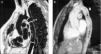

Figura 2. A) Resonancia spin-eco. Paciente de 22 años. Proyección sagital oblicua. Grupo A. Corrección término-terminal buena con arco normal. OP: zona de intervención; bandas: istmo coartación aorta descendente.B)Resonancia ecogradiente. Paciente de 16 años. Grupo A. Corrección con la técnica de plastia de subclavia + término-terminal (Álvarez). Ligera dilatación en la zona de la plastia (flecha blanca). Zona de sutura menor (estrella negra). P: arteria pulmonar; AoD: aorta descendente.

Figura 3. A) Angiorresonancia tridimensional. Reconstrucción. Grupo A: proyección sagital oblicua. Paciente de 7 años intervenido de recién nacido. Técnica término-terminal bien resuelta. Diámetro de la zona de intervención similar al de la aorta descendente a nivel diafragmático.B) Angiorresonancia tridimensional. Reconstrucción. Grupo A. Paciente de 21 años. Índices límite (0,80). Zona yuxtasubclavia en cirugía término-terminal ligeramente menor. OP: zona de intervención.